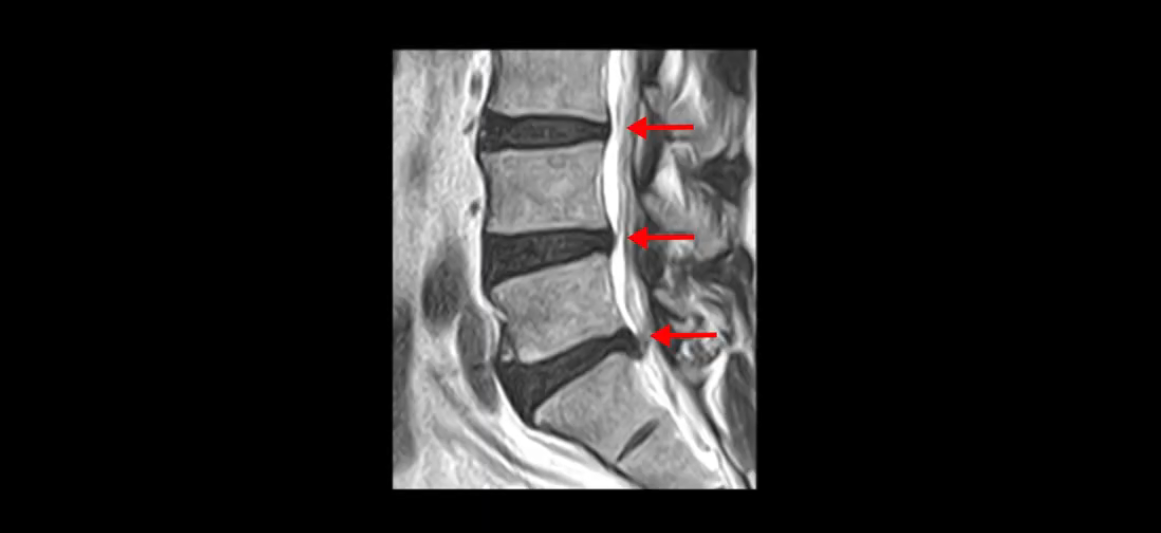

우선 이분 MRI를 잠깐 볼까요? 세 마디의 퇴행성 디스크가 있고

5번 1번이 파열되어 디스크 수핵이 밑으로 약간 흘러내려 있습니다.

단면을 보면 중앙 오른쪽으로 밀려 나왔는데 파열이 아주 심하지는 않습니다.

아주 심한 상태가 아니라서 방사통만 있지 마비, 즉 힘 빠짐은 없는 상태입니다. 이 정도의 크게 심하지 않은 디스크 탈출 정도라면 신경 주사 맞고 버티다 보면 좋아질 수도 있지만, 이 환자분은 보존한 지 10개월 후에 증상이 더 나빠집니다. 왜 그럴까요? 신경 주사도 전혀 듣질 않는데 어떻게 해야 수술 없이 좋아질 수 있을까요? 지금부터 설명해 드립니다.